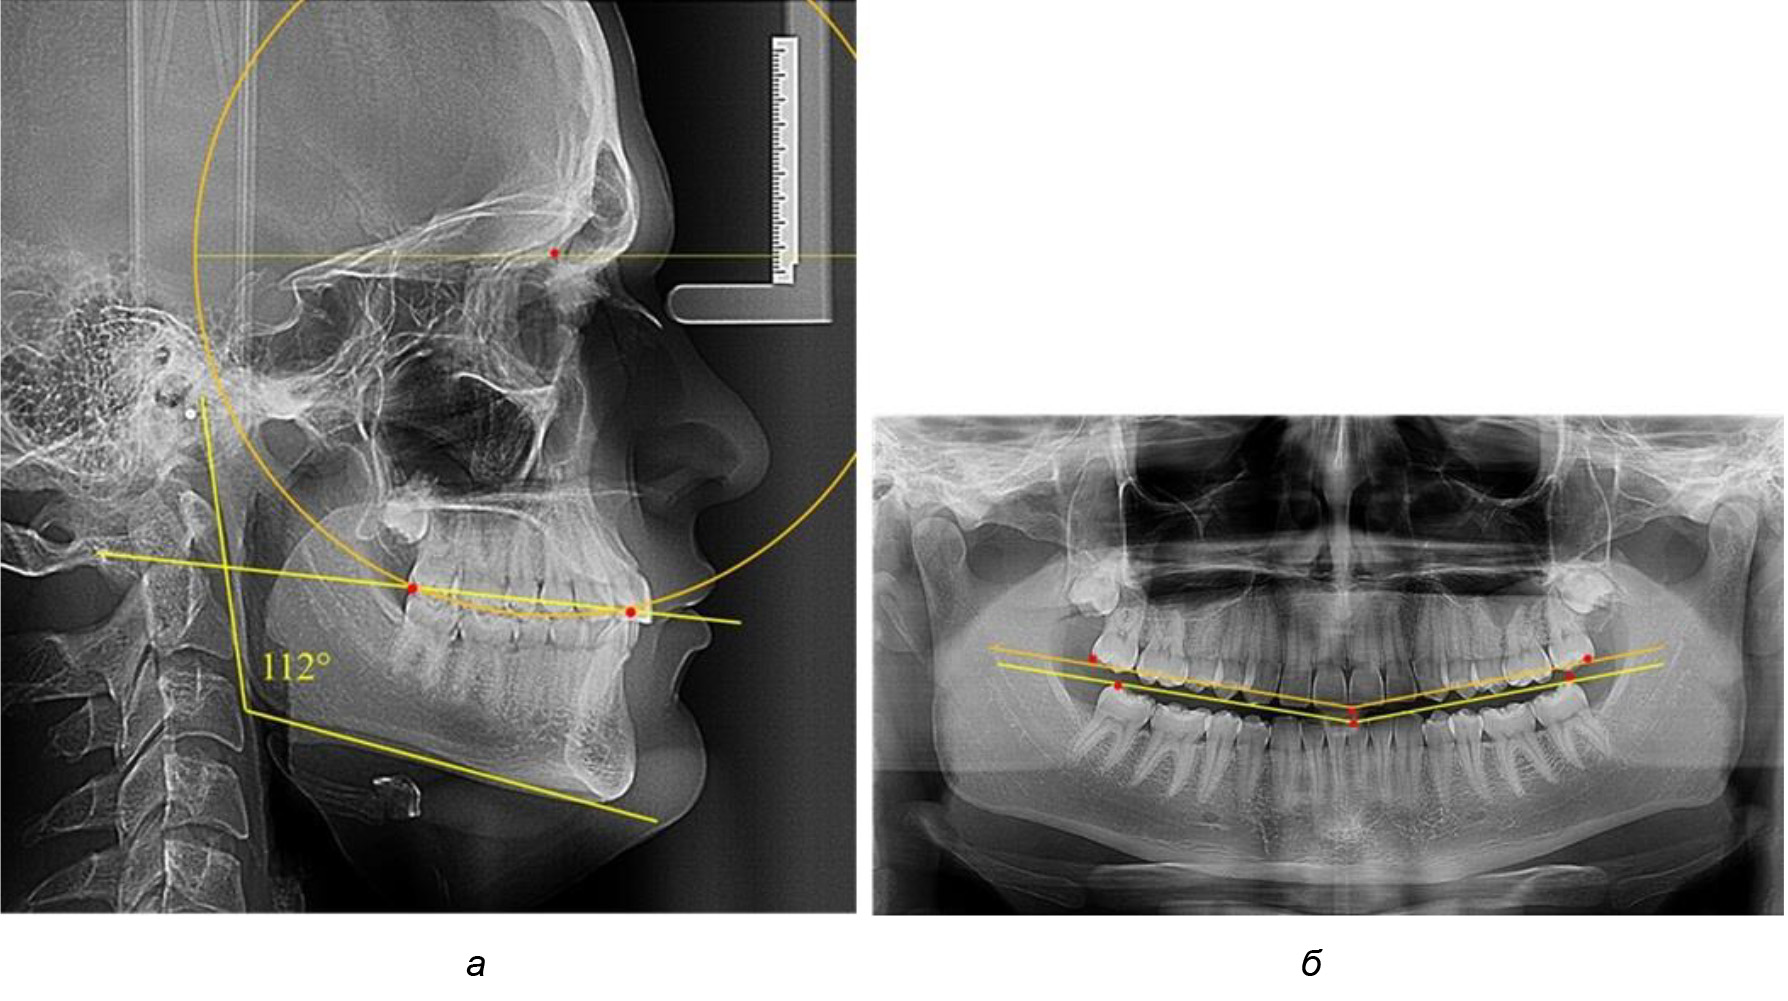

При анализе латеральных ТРГ устанавливали реперный окклюзионные точки в переднем и боковом отделе. Передняя точка устанавливалась на режущем крае нижнего медиального резца, которую в клинике ортодонтии обозначают как vPOcP. Дистальная точка второго нижнего моляра обозначалась как hPOcP. Измеряли расстояние между окклюзионными точками, что определяло сагиттальный размер окклюзионной линии. Использование программ PowerPoint позволило проводить окружность, проходящую по линии смыкания зубов через окклюзионные точки. Измеряли радиус окружности. Учитывая вариабельность размеров окклюзионной линии и радиуса окружности, определяли относительный показатель через отношение радиуса круга к длине сагиттального размера окклюзионной линии. Глубину окклюзионной кривой измеряли от точки наибольшей выпуклости до окклюзионной линии (рис. 1). На ортопантомограмме (ОПТГ) также соединяли окклюзионные точки правой и левой стороны и измеряли глубину окклюзионной кривой от точки наибольшей выпуклости до окклюзионной прямой линии. Результаты глубины кривой Spee сравнивали по данным ТРГ и ОПТГ.

Рис. 1. Метод определения кривой Spee на ТРГ (а) и на ОПТГ (б)

Анализ результатов показал, что глубина кривой Spee в среднем по подгруппе составил (4,12 ± 0,53) мм как при анализе ТРГ, так и ОПТГ.

Деление величины радиуса круга к длине окклюзионной линии составило 1,623 ± 0,02. Таким образом, для определения радиуса окружности, соответствующей кривизне окклюзионного контура боковой ТРГ, необходимо измерить расстояние между передней и задней окклюзионными точками и последующим умножением полученной величины на число Фибоначчи (рис. 2).